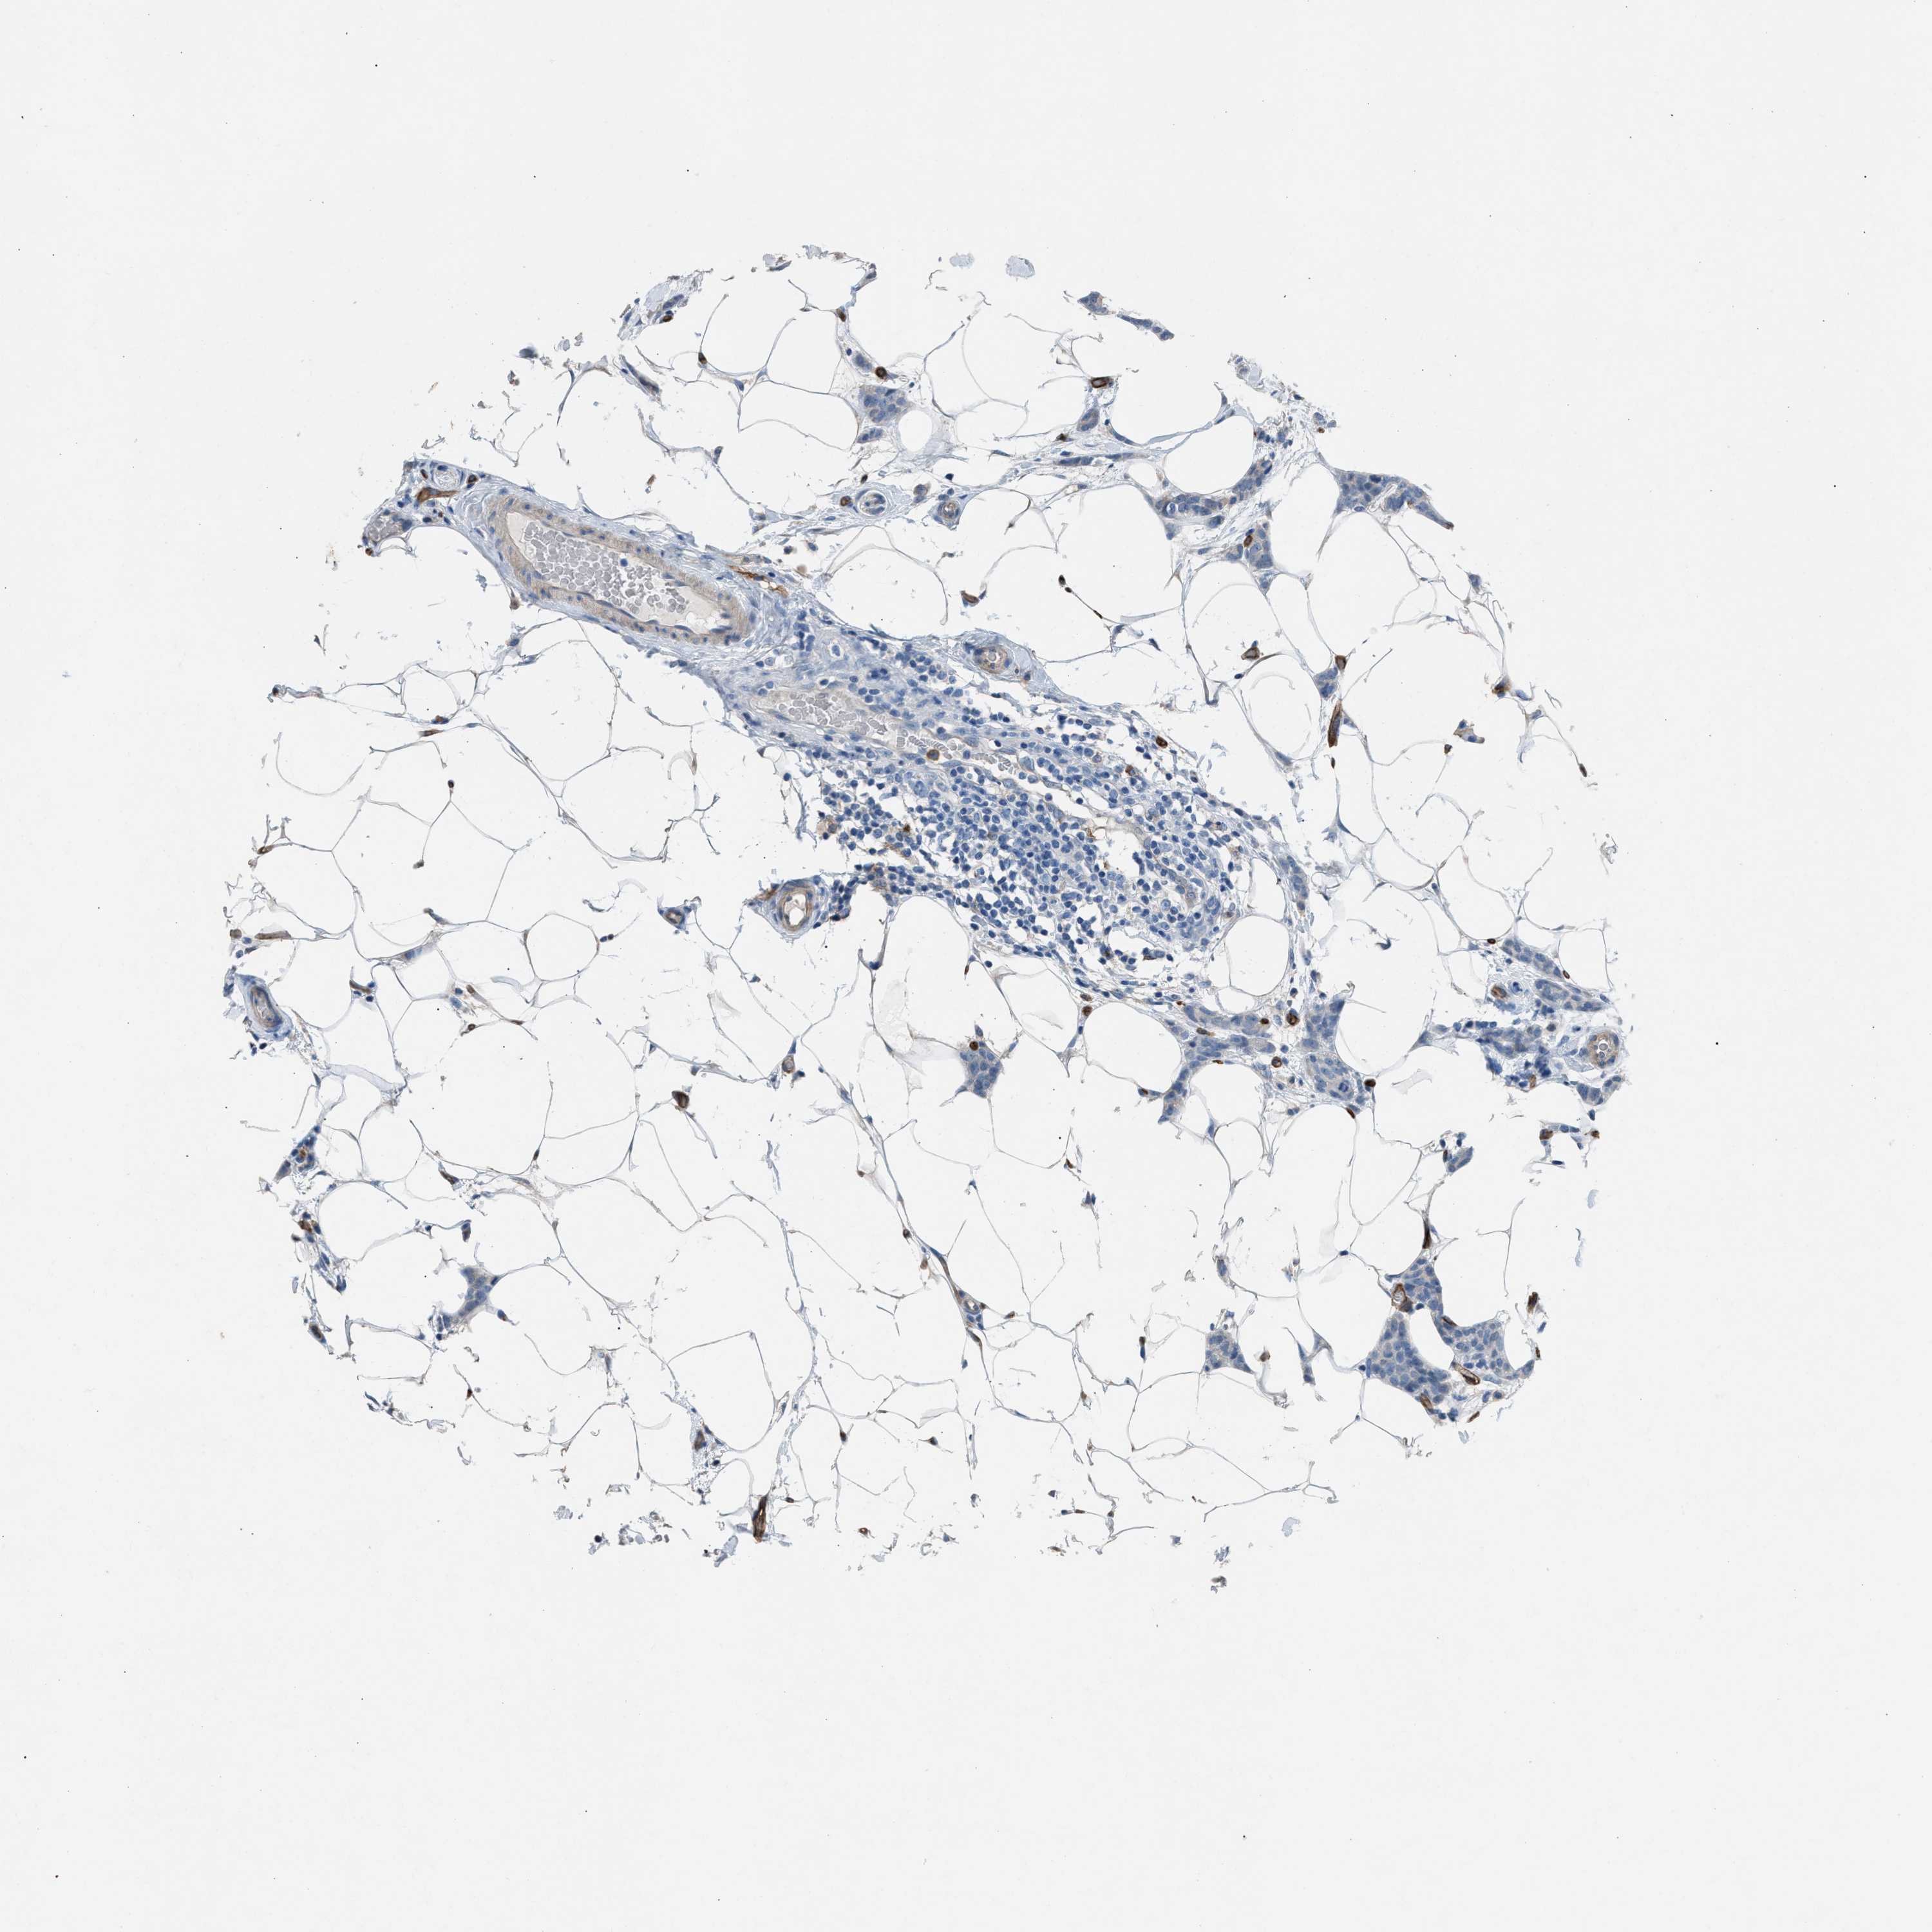

CANCER BREAST CANCER Show tissue menu

BRCA TCGA BRCA VALIDATION PROTEIN EXPRESSION